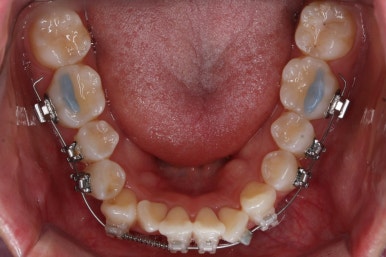

점점 가지런해지고 있습니다.

아래 앞니는 자리가 많이 부족했기 때문에 장치를 제대로 못 붙인 치아가 있고, 자리부터 확보해주고 있습니다.

윗니는 발치를 했고, 잇몸뼈에 미니스크류를 식립하여 앞니를 뒤로 당겨넣고 있습니다.

아랫니는 아직 덜 가지런해졌네요.